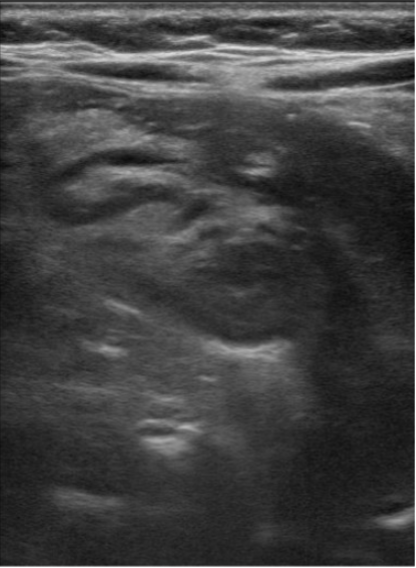

Intussisception appears as a non-compressible, target-shaped mass with concentric echogenic and hypoechoic rings on the transverse view and as a “pseudokidney” or “stack of pancakes” on the longitudinal views (Fig. 4 and Fig. 5 a,b,c).1,3,4 The important characteristic appearance on transverse scan is the presence of the central/eccentric and hyperechoic mesenteric fat, that is pulled with vessels and lymph nodes into the intussusception by the intussusceptum; which differentiates from other entities, such as bowel hematoma, stool, bowel wall edema, mass, or even a psoas muscle.9 Doppler ultrasonography can also be useful to detect and evaluate blood flow. The absence of flow is a sign that surgical reduction may be necessary.4

(Figure 6a: Left) (Figure 6b: Center) (Figure 6c: Right)

Figure 6a-6c. Right lower quadrant ultrasound, transverse (a) and longitudinal views (b). (c) Layered 3.4 cm appearance mass is identified in the right lower quadrant, interposed hypo/hyper echogenic layers, with central hyperechoic mesentery fat, representing the intussusceptum (arrow).